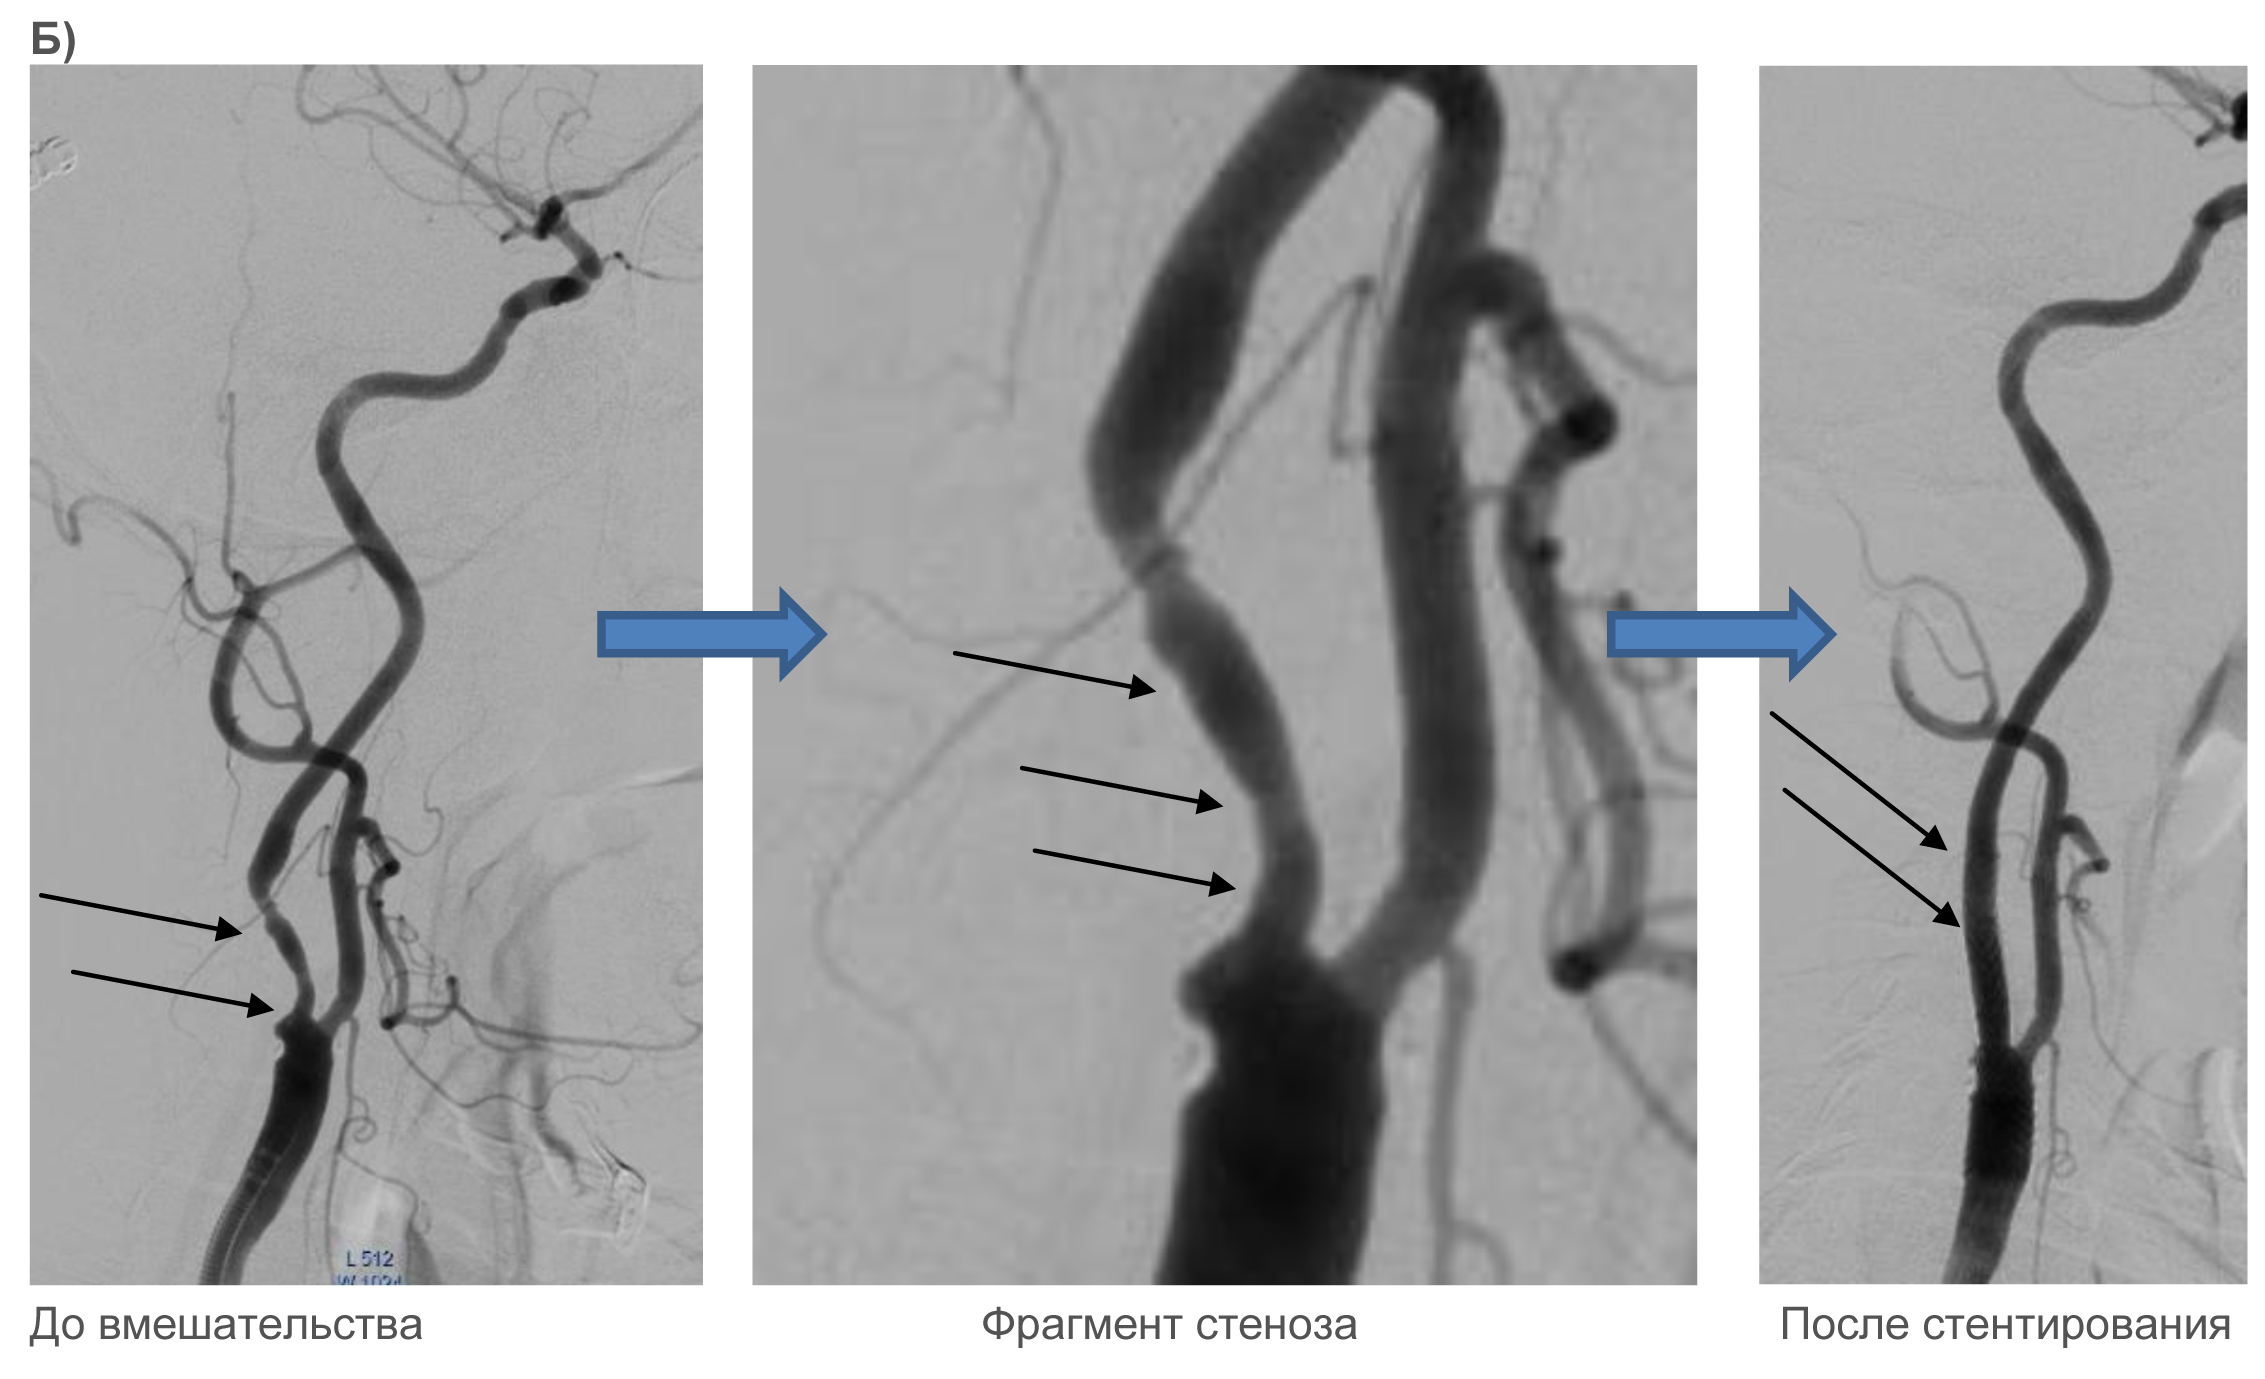

Клинические примеры:

Для иллюстрации клинических примеров выполненных стентирований сонных артерий отсутствует необходимость подробного описания состояния пациентов до и после проведенного вмешательства, т.к. самочувствие пациента может значимо не меняться. Основной целью вмешательства является профилактика инсульта.

Ниже – несколько наглядных примеров выполнения стентирования: